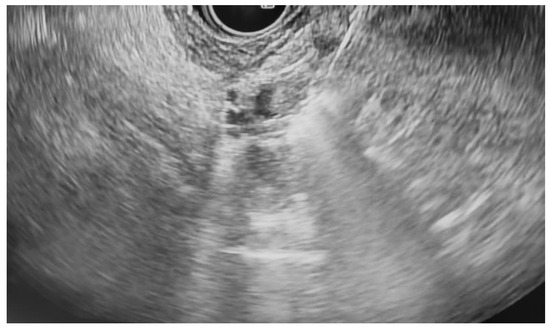

Additional notable cases in our series included a pancreatic cyst with a high-grade dysplastic nodule in an 80-year-old female patient. The initial 11.0 × 10.0 mm nodule was completely ablated (0.0 × 0.0 mm residual) after a single RFA session using a 19-gauge/7 mm needle at 50 watts of power for three applications with no complications (Figure 1, Figure 2 and Figure 3). Similarly, a 41-year-old male with a 13.5 × 8.5 mm insulinoma in the pancreatic neck who presented with multiple syncopal episodes secondary to hypoglycemia achieved complete radiologic and biochemical resolution after a single RFA session using a 19-gauge/5 mm needle at 10 watts of power for two applications (Figure 4, Figure 5 and Figure 6), with no adverse events and normalization of his insulin and glucose levels post-procedure and the resolution of his syncope.

Figure 1. Pancreatic cyst with mural nodule and high-grade dysplasia on EUS.

Jcm 14 03958 g001